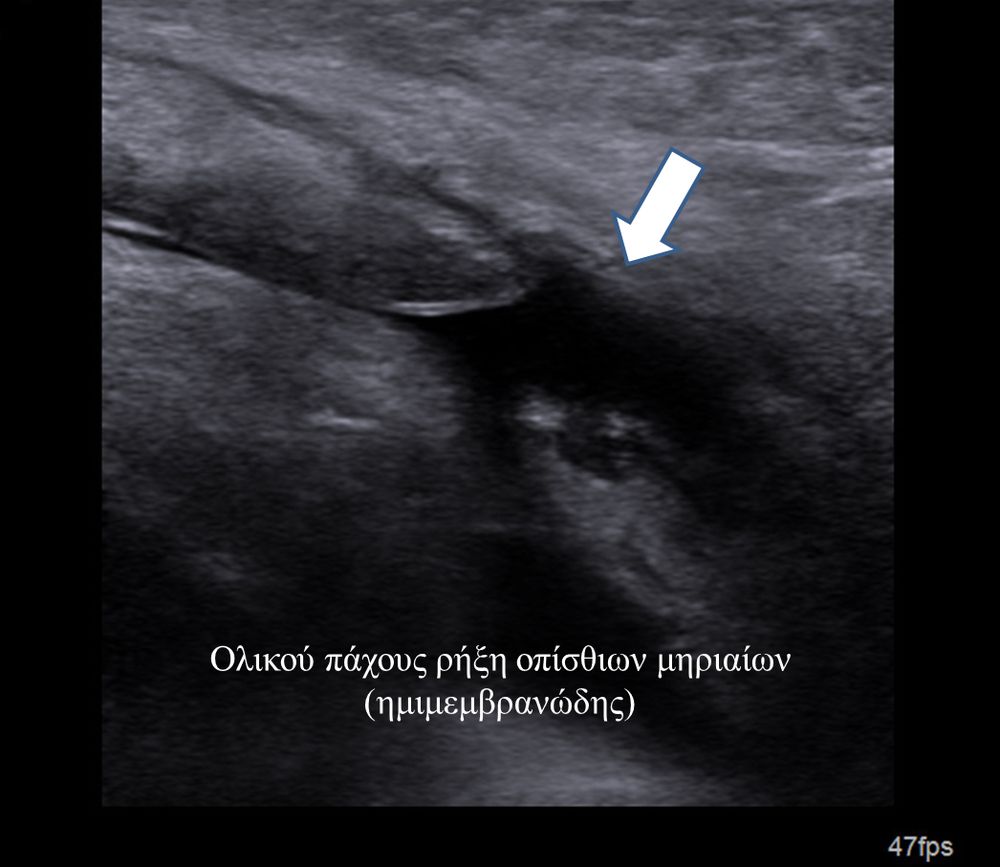

Είναι μια νέα μέθοδος που χρησιμοποιεί υψηλής ευκρίνειας υπερήχους για τη διάγνωση μυοσκελετικών παθήσεων που αφορούν τένοντες, μυς, συνδέσμους, νεύρα και περιφερικές αρθρώσεις. Η μέθοδος αναπτύχθηκε τα τελευταία χρόνια και αποτελεί αναπόσπαστο μέρος στη διαφορική διάγνωση παθήσεων που αφορούν τηνορθοπαιδική, αθλητιατρική, ρευματολογία και παιδιατρική.

Πρόκειται για υπερηχογράφημα υψηλής ευκρίνειας που επιτρέπει την λεπτομερέστατη απεικόνιση (σε επίπεδο χιλιοστού) ακόμη και πολύ μικρών/επιφανειακών ανατομικών δομών και απαιτεί ειδικό υπερηχογραφικό εξοπλισμό καθώς και εξειδίκευση του ακτινολόγου. Η εξέταση γίνεται με δυναμικό τρόπο, δηλ εκτελούνται δοκιμασίες κίνησης του μέλους που πάσχει, ώστε να αποκαλυφθεί η παθολογίαακόμη και όταν δεν είναι εμφανής σε θέση ηρεμίας. Επιπλέον, η εξέταση είναι ανώδυνη και ασφαλής και δεν περιλαμβάνει ακτινοβολία (CT), μαγνητικό πεδίο (MRI) ή παραμονή σε κλειστό χώρο και είναι πολύ ανεκτή τόσο σε ενήλικες όσο και σε παιδιά.

- Παθήσεις Ώμου (πχ ρήξη στροφικού πετάλου)